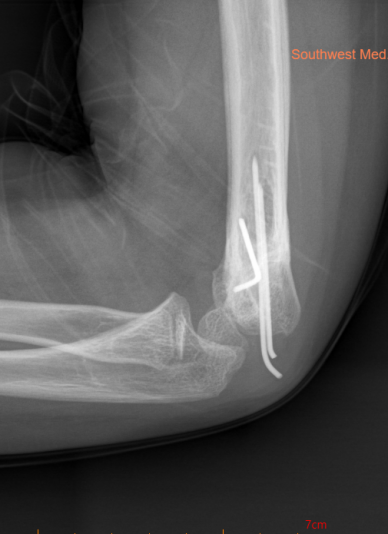

肱骨髁上骨折闭合复位经皮克氏针内固定术

1.相比于传统的开放手术,闭合穿针技术的切口小,对软组织的损伤小,术后恢复快;

2.髓内针固定能够提供稳定的固定作用,有助于骨折部位的复位和愈合;